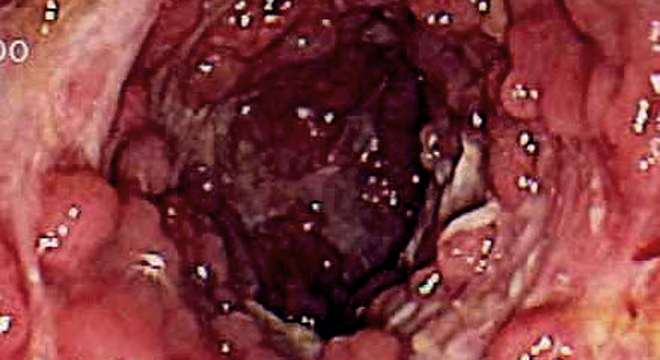

Morbus Crohn: Darmspiegelung

• Darmspiegelung (Koloskopie) und Gewebsentnahmen.